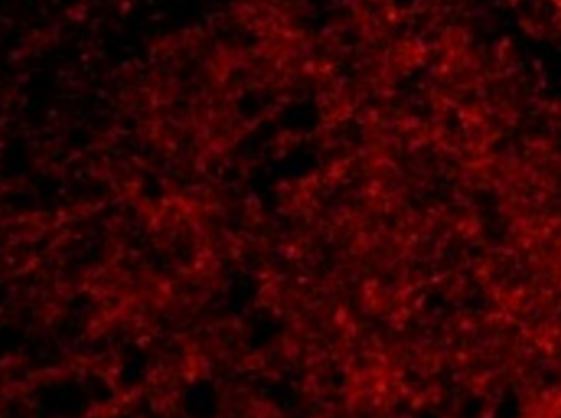

ARG46400 anti-Presenilin 1 / PS1 (CTF) antibody ICC/IF image

Immunofluorescence: Human brain stained with ARG46400 anti-Presenilin 1 / PS1 (CTF) antibody.